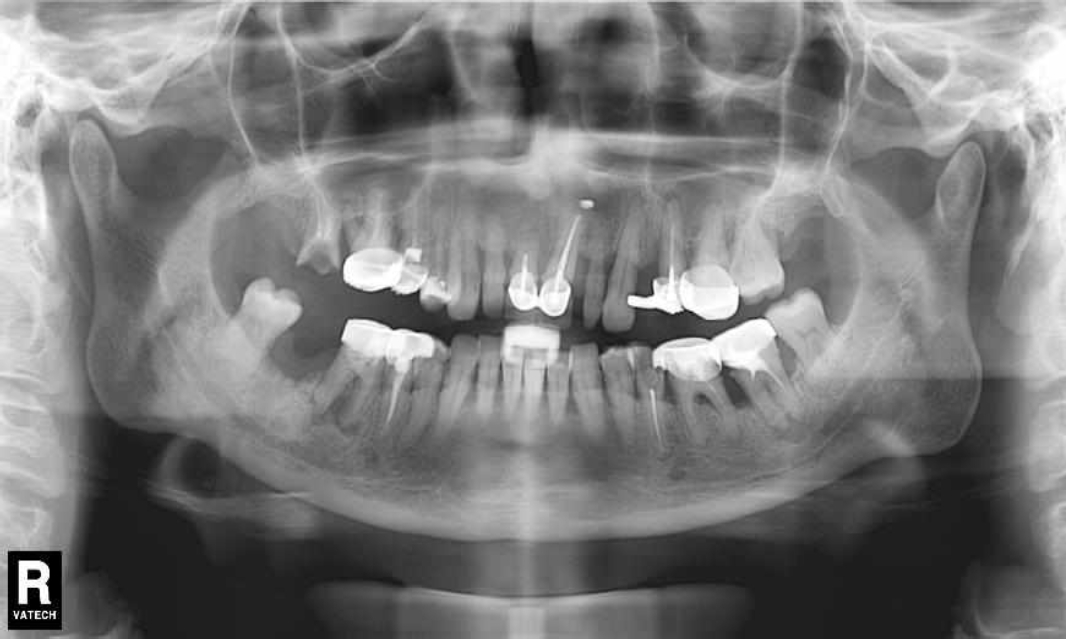

Ранее у пародонтолога не наблюдалась. При осмотре выявлены: неудовлетворительная индивидуальная гигиена полости рта, пародонтальные карманы до 7 мм, обильная кровоточивость и гноетечение из пародонтальных карманов, подвижность зубов 4.2, 4.1, 3.1, 3.2 II степени, обильные над- и поддесневые зубные отложения (рис. 1). На ортопантомограме отмечается резорбция костной ткани до ½ длины корня, очаги остеопороза (рис. 2). Пациенту был поставлен диагноз хронический генерализованный пародонтит тяжелой степени тяжести. При осмотре была составлена пародонтограмма с использованием компьютерного зондирования (рис. 3).

Рис. 1. Внешний вид

Рис. 2. Ортопантомограмма исходной ситуации пациента состояния полости рта